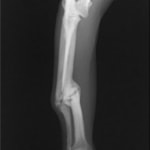

症例:交通事故による椎体脱臼

柴犬:9歳、避妊雌

交通事故直後、胸腰部に激しい疼痛、両後肢に完全麻痺を認め、シェフシェリントン徴候を呈していました。レントゲン検査において、第11-12胸椎間の脱臼が認められました。

脊髄の減圧、脊柱管の再構築・安定化を目的に、片側椎弓切除術およびMatrixMANDIBLE Plateによる椎体固定を実施しました。

隣接椎体を架橋するようにプレートを設置しました。

術後レントゲン写真